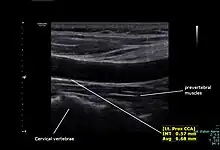

Left proximal common carotid artery intimal thickness (IMT) measurement and diameter by using doppler ultrasound

The condition and health of the common carotid arteries is usually evaluated using Doppler ultrasound, CT angiography or phase contrast magnetic resonance imaging (PC-MRI).

Typically, blood flow velocities in the common carotid artery are measured as peak systolic velocity (PSV) and end diastolic velocity (EDV).

In a study of normative men aged 20-29 years, the average PSV was 115 cm/sec and EDV was 32 cm/sec. In men 80 years and older, the average PSV was 88 cm/sec and EDV was 17 cm/sec.[7]

The intima-media thickness of the carotid artery wall is a marker of subclinical atherosclerosis and it increases with age and with long-term exposure to particulate air pollution. [9]